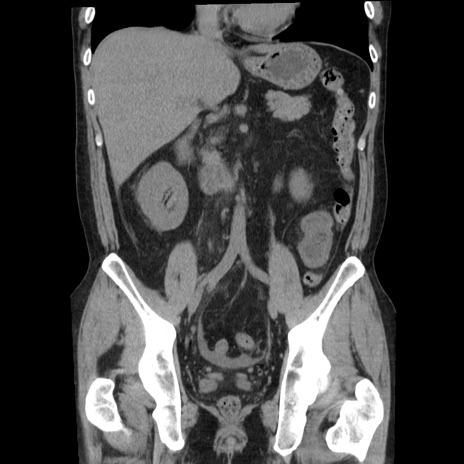

症例29(冠状断像)

【症例】40歳代男性

【現病歴】2日前から胃痛あり。徐々に周期的な激痛に変化した。本日になっても激痛があるため受診。

【身体所見】意識清明、BT 38-39℃台あり、腹部:膨満、やや硬、右下腹部に圧痛あり。

【データ】WBC 8500、CRP 23.26